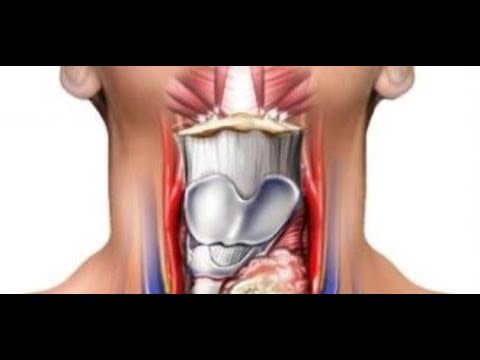

Фотографии опухоли медуллярной аденокарциномы

Раздел: Снимки-откровения